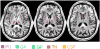

Magnetic susceptibility provides an important contrast mechanism for MRI. Increasingly, susceptibility-based contrast is being exploited to investigate brain tissue microstructure and to detect abnormal levels of brain iron as these have been implicated in a variety of neuro-degenerative diseases. However, it remains unclear to what extent magnetic susceptibility-related contrast at high field relates to actual brain iron concentrations. In this study, we performed susceptibility weighted imaging as a function of field strength on healthy brains in vivo and post-mortem brain tissues at 1.5 T, 3 T and 7 T. Iron histology was performed on the tissue samples for comparison. The calculated susceptibility-related parameters R(2)(*) and signal frequency shift in four iron-rich regions (putamen, globus pallidus, caudate, and thalamus) showed an almost linear dependence (r>or=0.90 for R(2)(*); r>or=0.83 for phase, p<0.01) on field strength, suggesting that potential ferritin saturation effects are not relevant to susceptibility-weighted contrast for field strengths up to 7 T. The R(2)(*) dependence on the putative (literature-based) iron concentration was 0.048 Hz/T/ppm. The histological data from brain samples confirmed the linear dependence of R(2)(*) on field strength and showed a slope against iron concentration of 0.0099 Hz/T/ppm dry-weight, which is equivalent to 0.05 Hz/T/ppm wet-weight and closely matched the calculated value in vivo. These results confirm the validity of using susceptibility-weighted contrast as an indicator of iron content in iron-rich brain regions. The absence of saturation effects opens the way to exploit the benefits of MRI at high field strengths for the detection of iron distributions with high sensitivity and resolution.